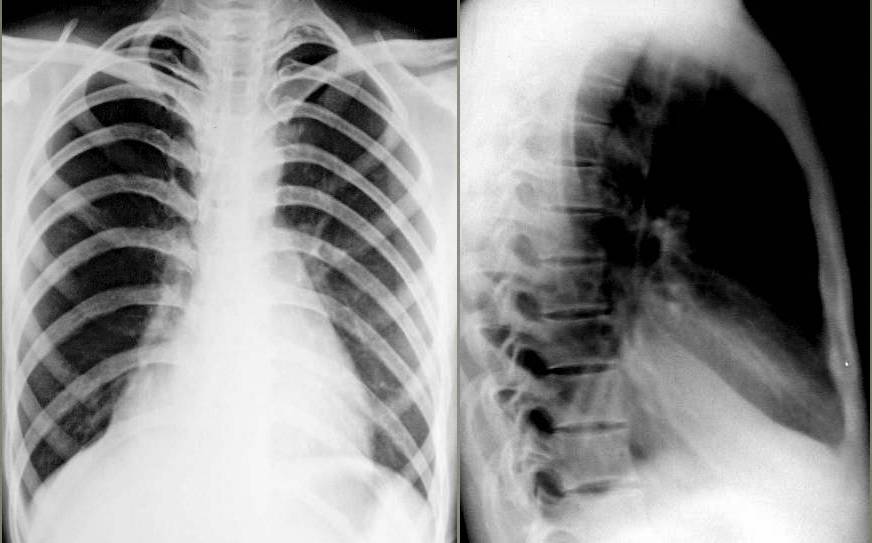

↓ 患儿9岁,咳嗽、高热。左肺炎症并左上肺肺实变、不张(X、CT)